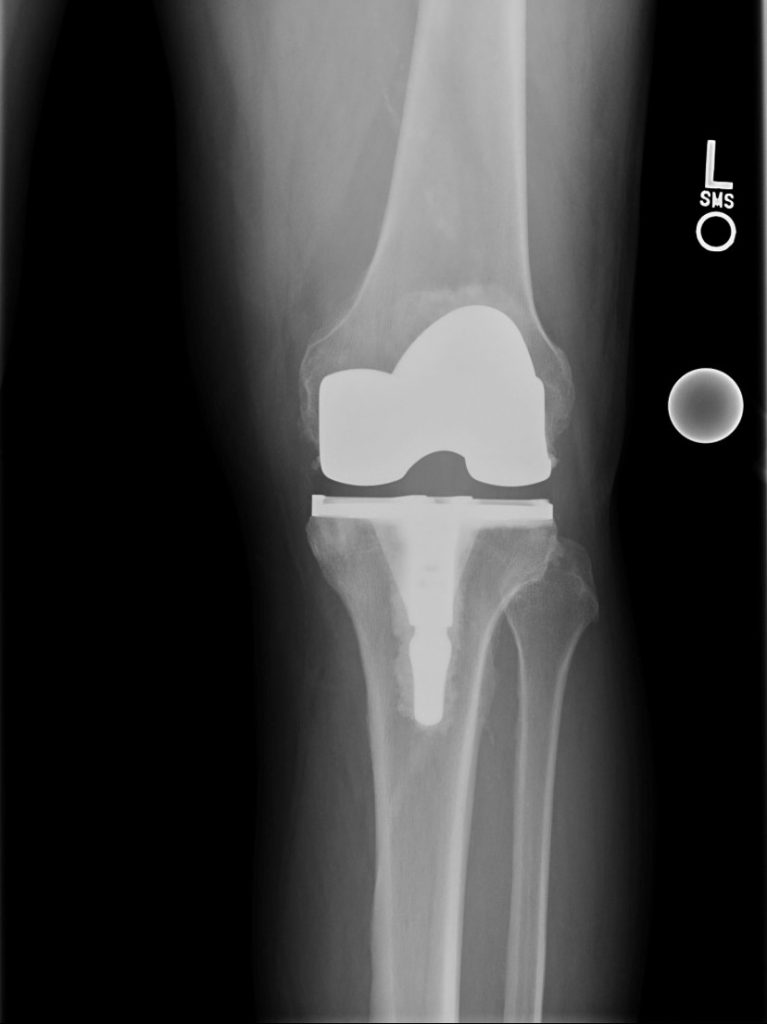

Knee Replacement

In 2 consecutive years I had both my knees replaced by Dr Elizabeth Gausden and as expected, there was considerable pain involved. After all, it is major surgery. But with the experience, professionalism and care of the surgical team and after-care support staff nurses, medical assistants and physical therapists, I am both happy and grateful that I chose HSS. I would not hesitate to tell anyone who asks that I recommend HSS as the best orthopedic hospital there is. To quote Dr Gausden, I now have a ‘matching set’.